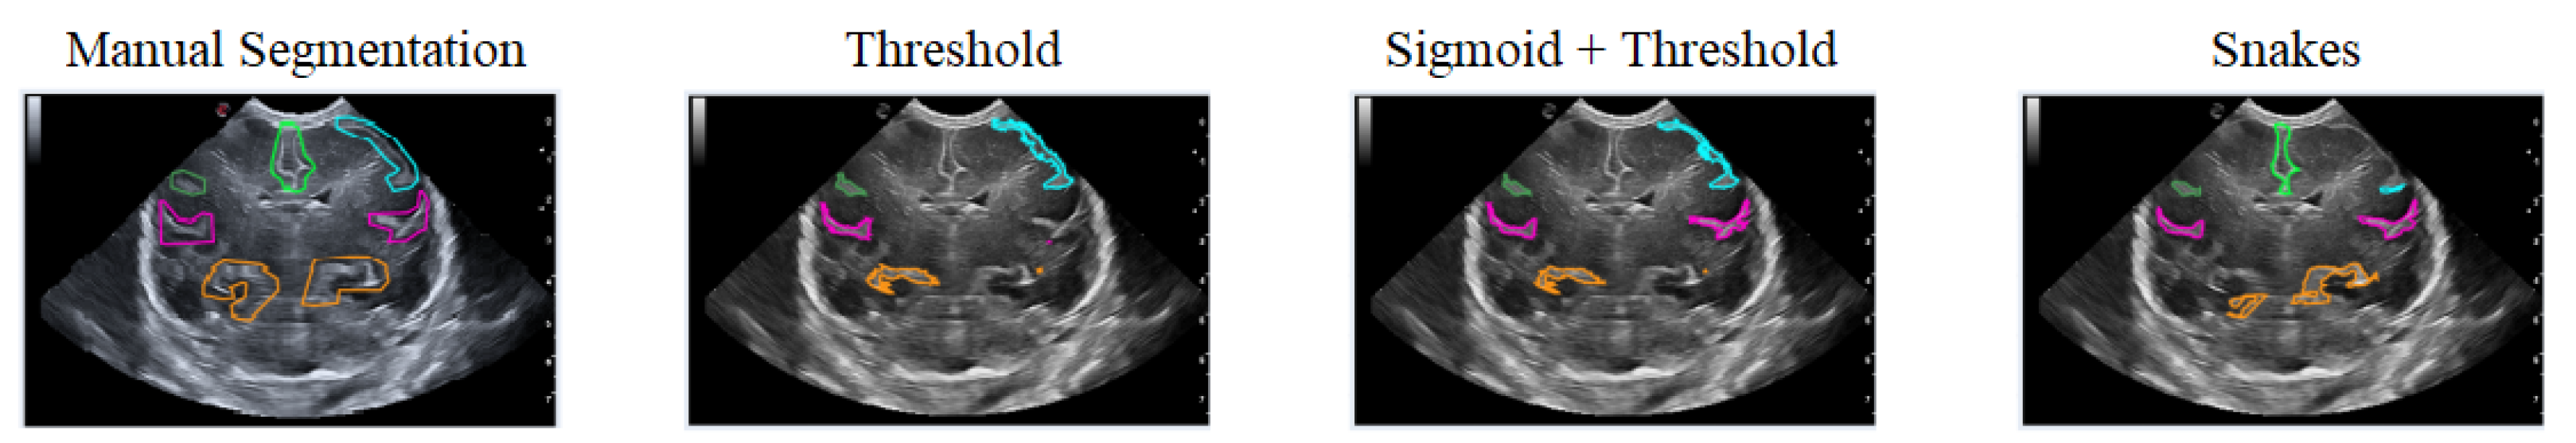

The first case analyzed used an image of a premature infant at week 29 of gestation, in which several furrows have been segmented, as shown in Figure 16. Each color represents a particular groove in which manual segmentation has been applied in the first image or one of the methods applied in the following images, in the order of Threshold, Sigmoid + Threshold, and Snakes.

Figure 16 shows that when applying the Threshold method (second and third images), there is not much variation in obtaining the segmentation. However, applying the Sigmoid preprocessing was able to segment the pink-colored groove on the right side. In contrast, the Snakes method (fourth image) was able to segment an orange-colored groove in the lower right part that had not been segmented with the Threshold method.

Figure 16. Examples of segmentation of different grooves in an ultrasound scan of a baby at week 29 of gestation and c4 coronal section.